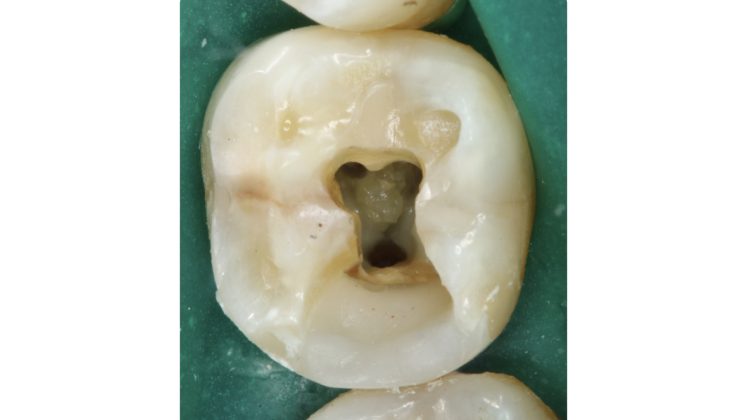

Il pavimento della camera pulpare si presenta sempre con un aspetto più scuro ed opaco rispetto al tessuto calcificato che tende ad essere lucido con un effetto che potremmo definire “vetrificato” (Figure 15-20).

Talvolta la differenza è evidente, in altri casi molto più sottile e quindi anche le difficoltà incontrate possono essere maggiori.

Asciugare la camera pulpare è il primo passaggio da compiere per poter visualizzare in modo netto le differenze.